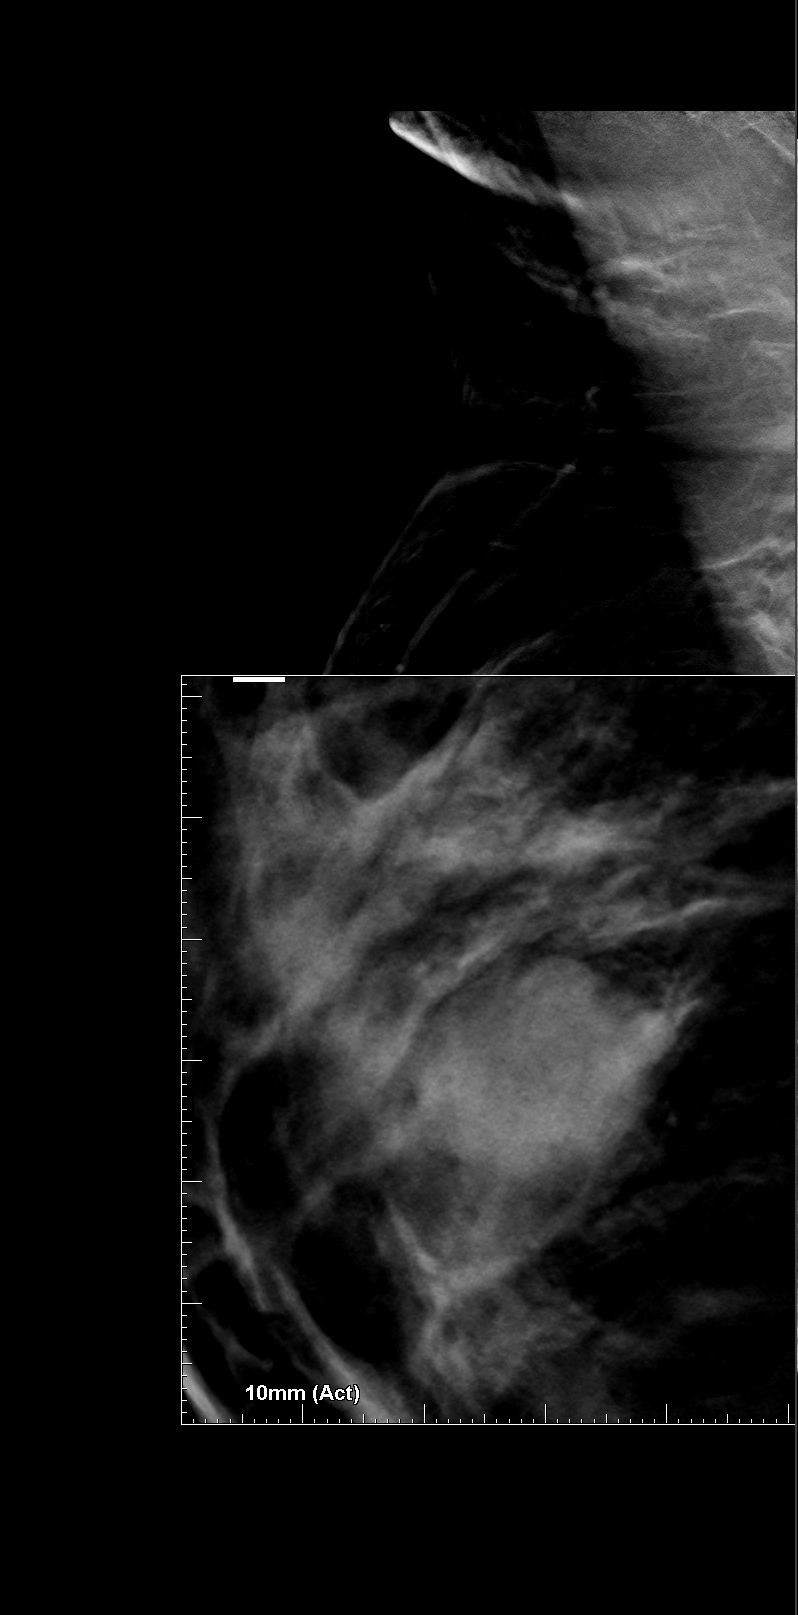

Bilateral Digital mammography , Craniocaudal (CC) and Mediolateral oblique (MLO) view with tomosynthesis images revealed a round shaped, equal density mass with indistinct margin in lower outer quadrant. No suspicious microcalcifications was seen. No significant axillary lymph nodes were present. A high resolution ultrasound of the right breast showed a round shaped, heterogeneously hypoechoic mass with irregular margin, small cystic spaces within and posterior acoustic enhancement, measuring about 1.6x1.9x1.5cm at 7 O’clock position. Mild internal vascularity was noted on colour doppler images. Right axilla showed suspicious lymph nodes with loss of fatty hilum and thickened cortex.